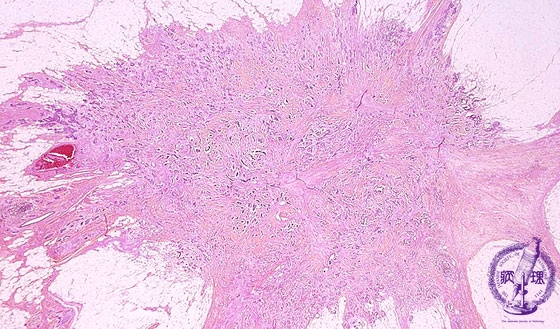

- ★(6)Invasive ductal carcinoma(Scirrhous carcinoma)

Microscopic image(HE stain, low power view):Tumor margin irregular with fluffing, representing the infiltration to adjacent adipose tissue.